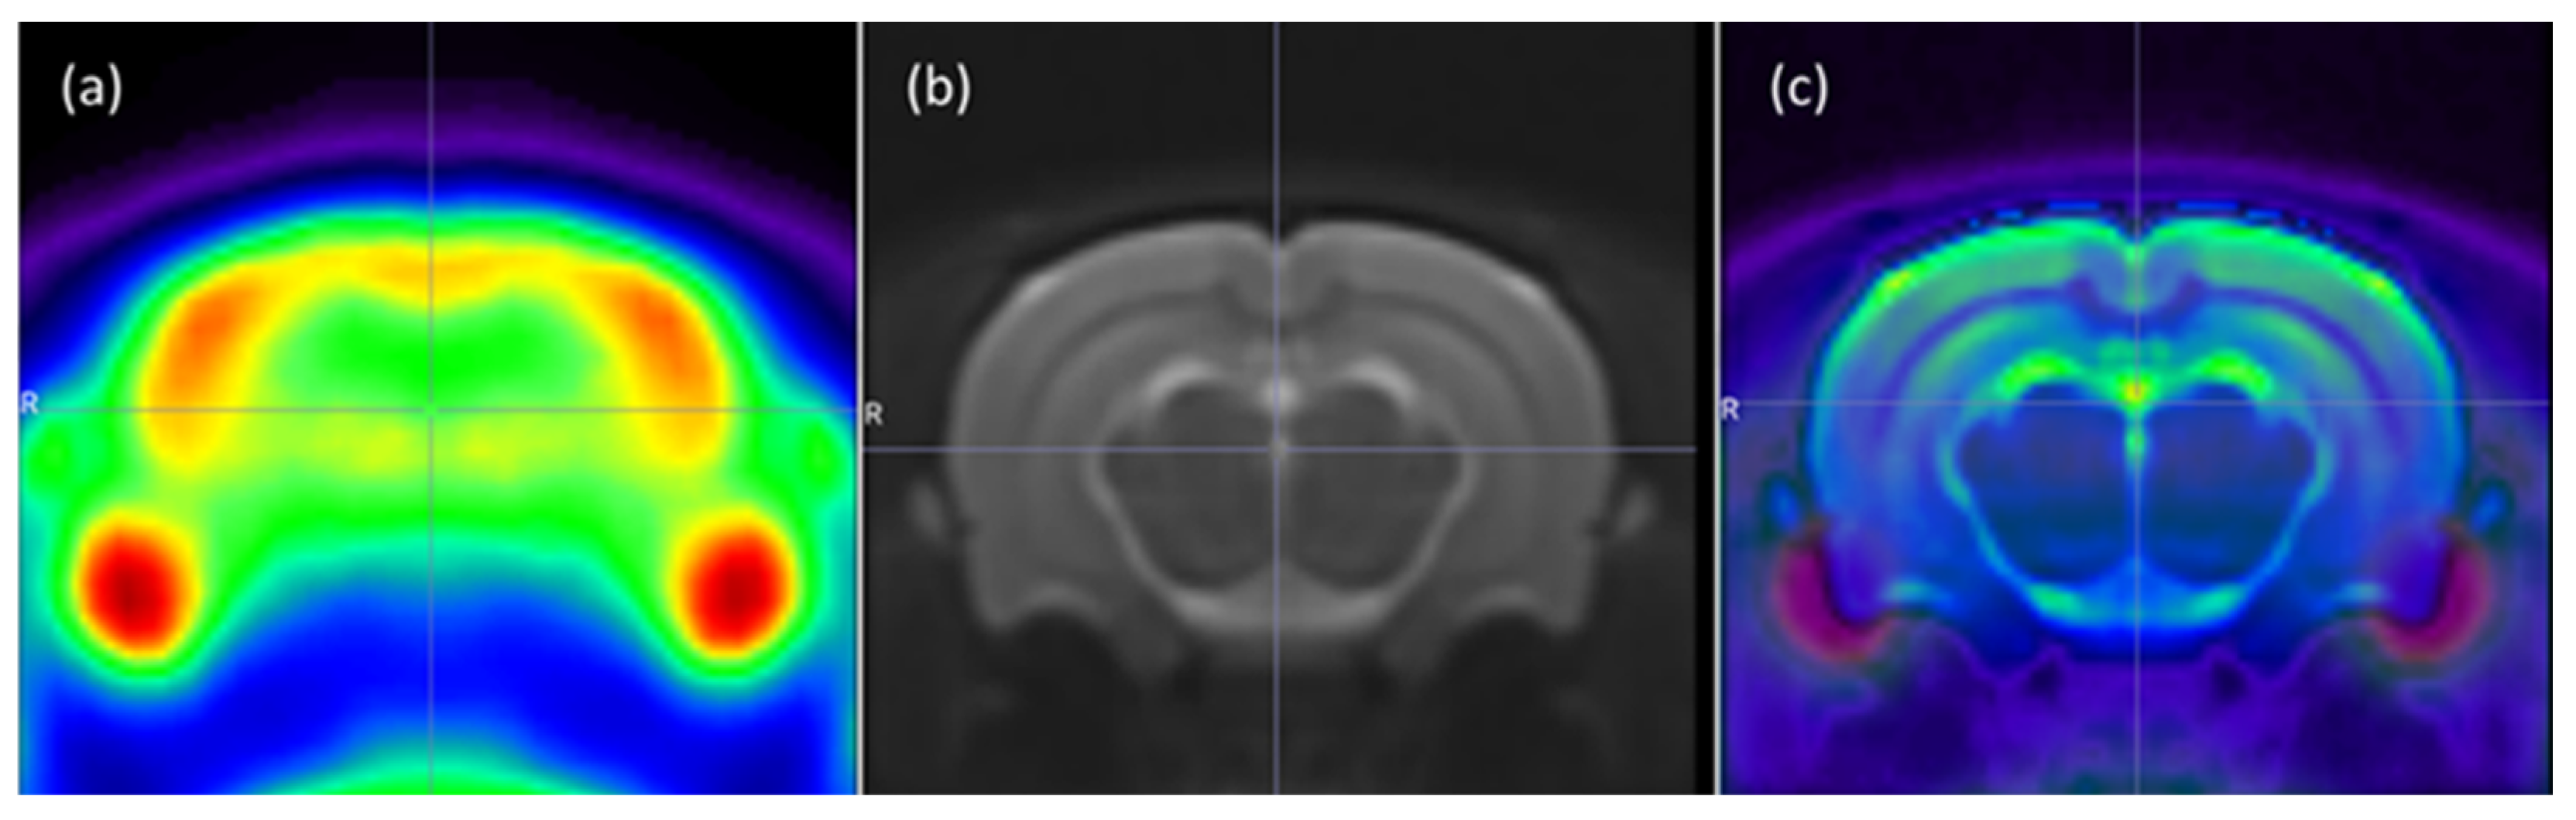

2.4.2. 18F-FDG Brain PET/MRI—Image Acquisition

2.4.3. Image Processing

3.2. Effects of Matricaria Chamomilla Extract on Brain Metabolism and Image Quantifications